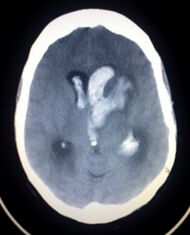

| CT scan of a spontaneous intracranial hemorrhage | |

يعتمد بصفة رئيسة على تصوير الدماغ، ومن أكثر طرق التصوير استعمالاً التصوير الطبقي المحوري (الشكل 3)، وبدرجة أقل المرنان المغنطيسي. وجدير بالذكر أن تصوير الدماغ قد يخفق في إظهار النزف في نحو 5% من المرضى، وفي هذه الحالة يمكن اللجوء إلى استقصاء آخر هو البزل القطني للسائل الدماغي الشوكي. وتظهر دراسة السائل وجود أعداد كبيرة من الكريات الحمر، مما يثبت حدوث النزف.